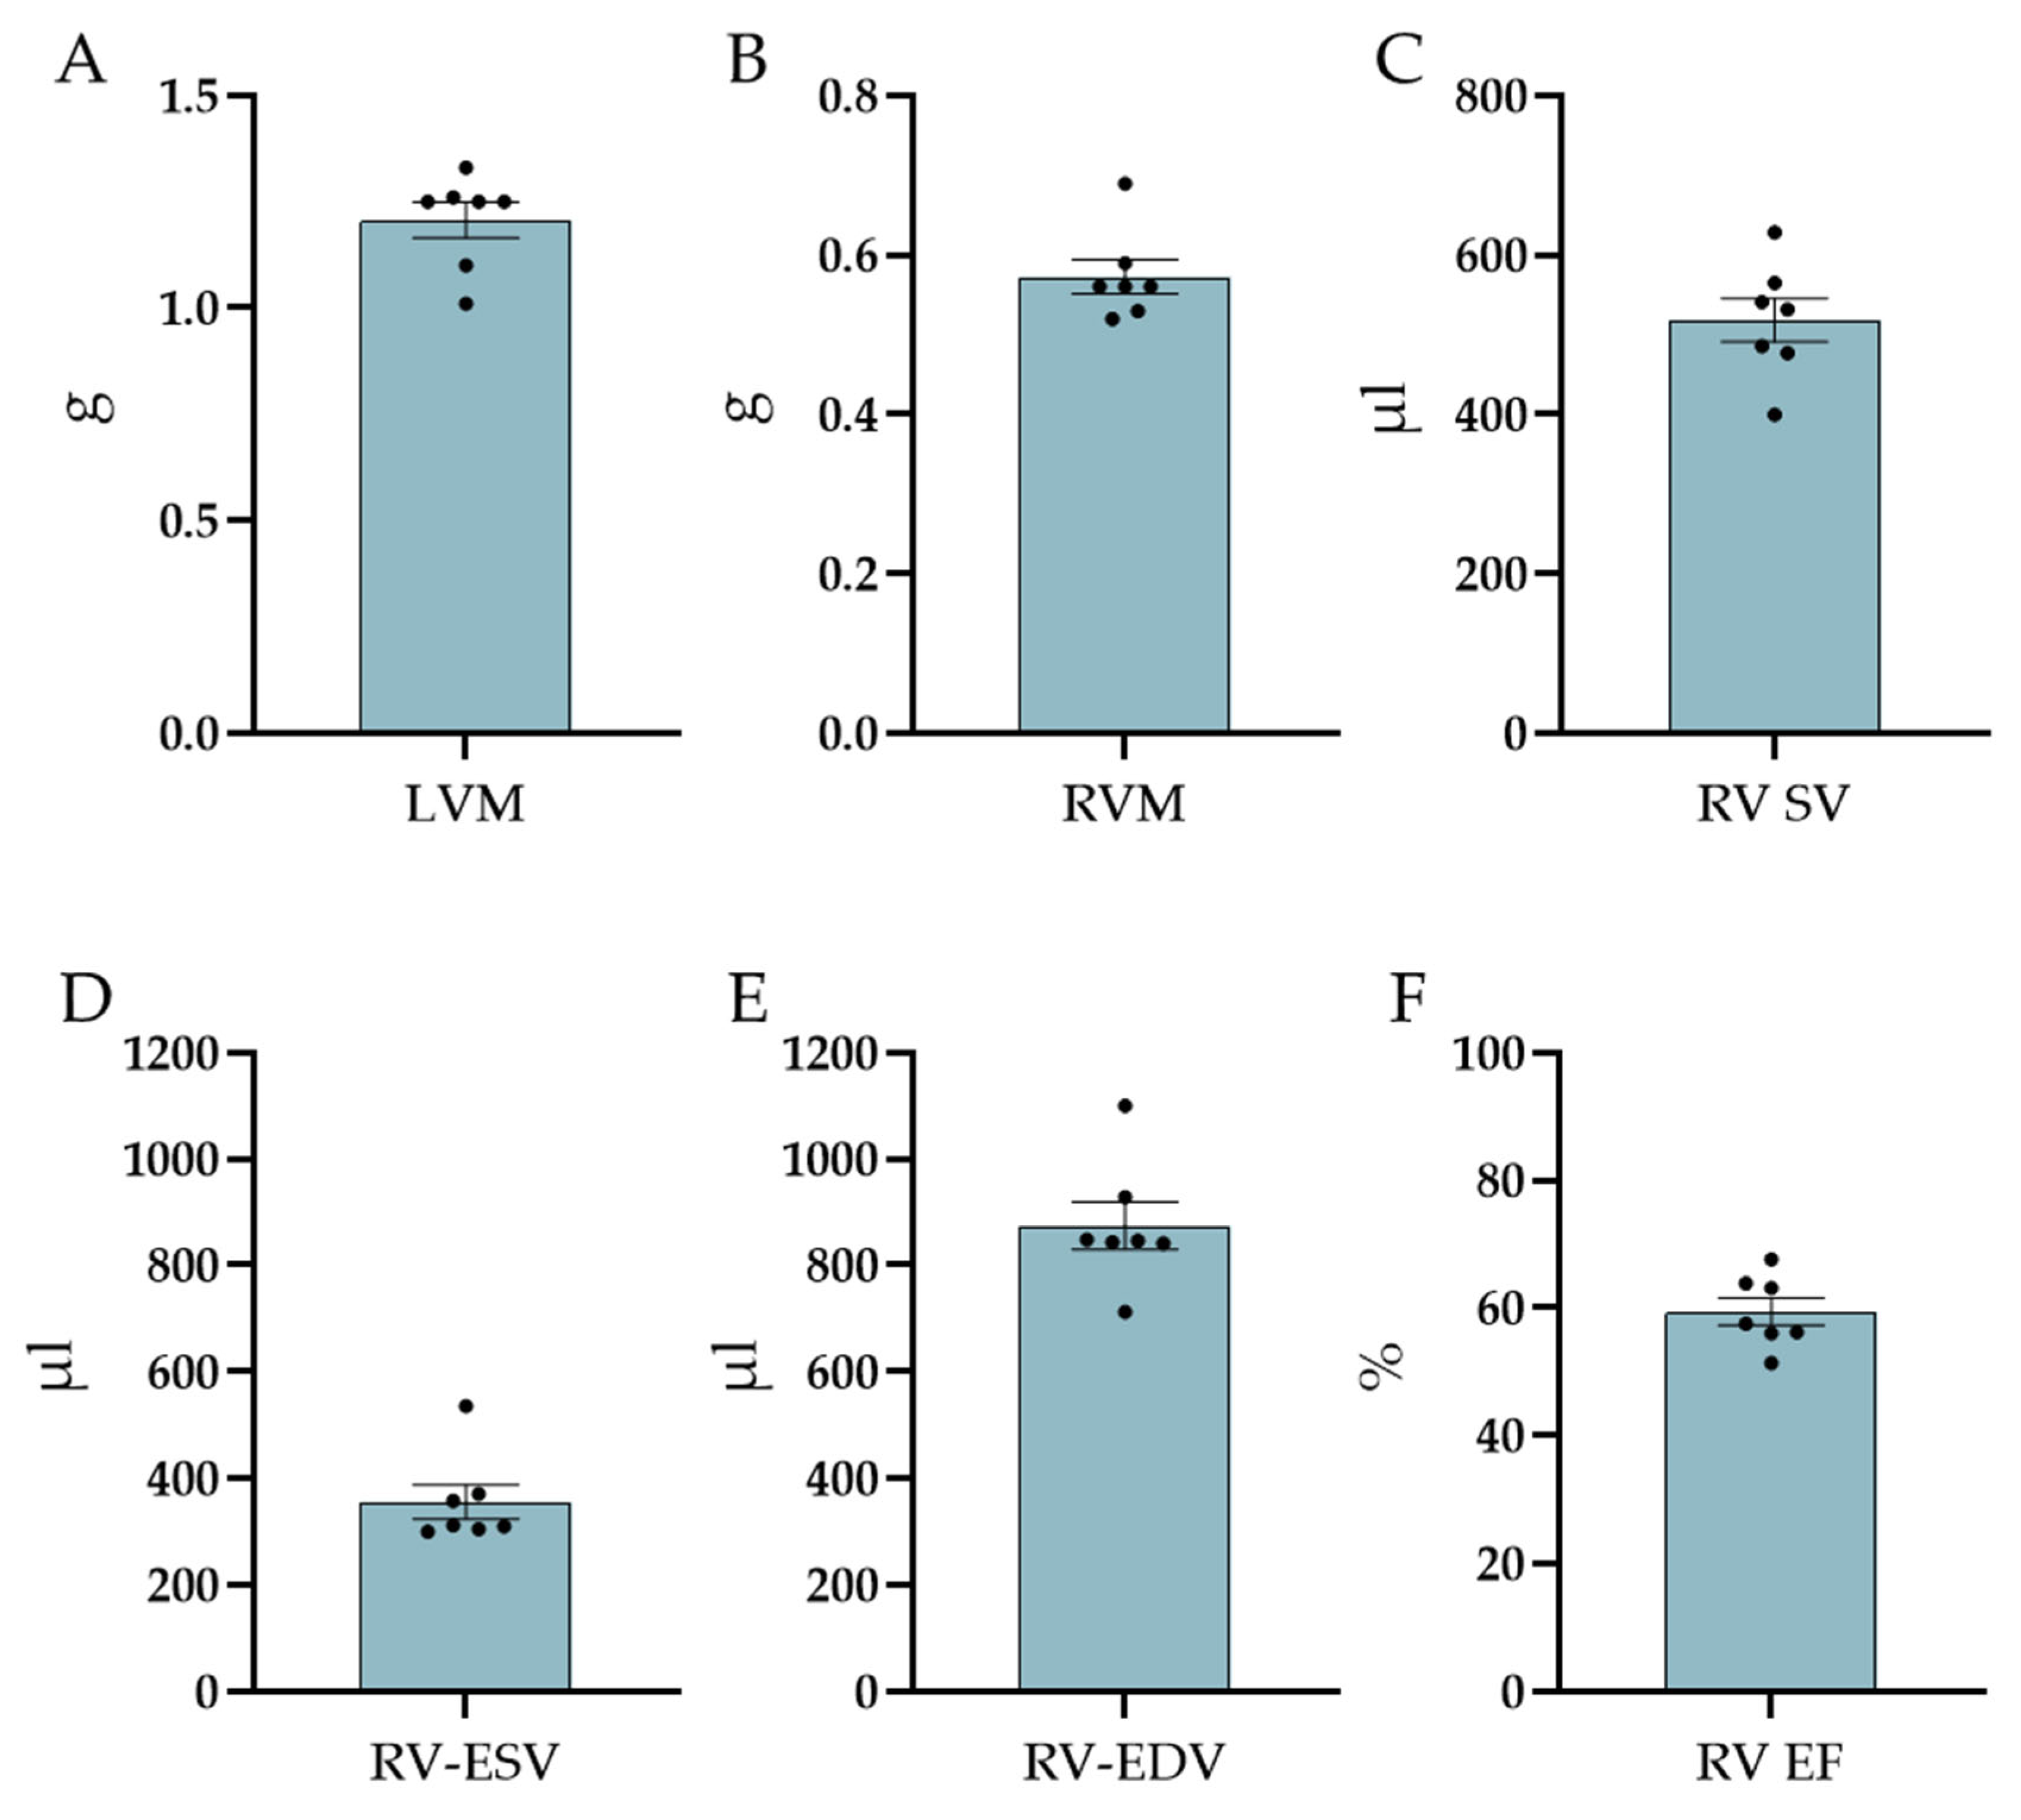

3.2. MRI Measurements